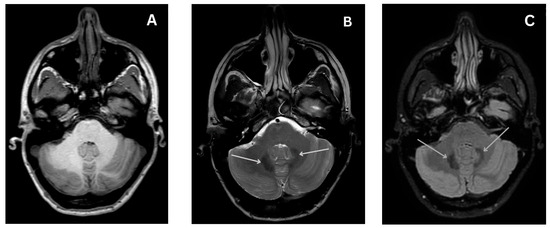

Early Diagnosis of Central Disorders Mimicking Horizontal Canal Cupulolithiasis

Background: Horizontal Canal Cupulolithiasis (hc-BPPV-cu) can mimic a pathology of central origin, so a careful examination is essential to prevent misdiagnosis. Methods: Retrospective cross-sectional cohort study of 45 patients suffering from suspec...